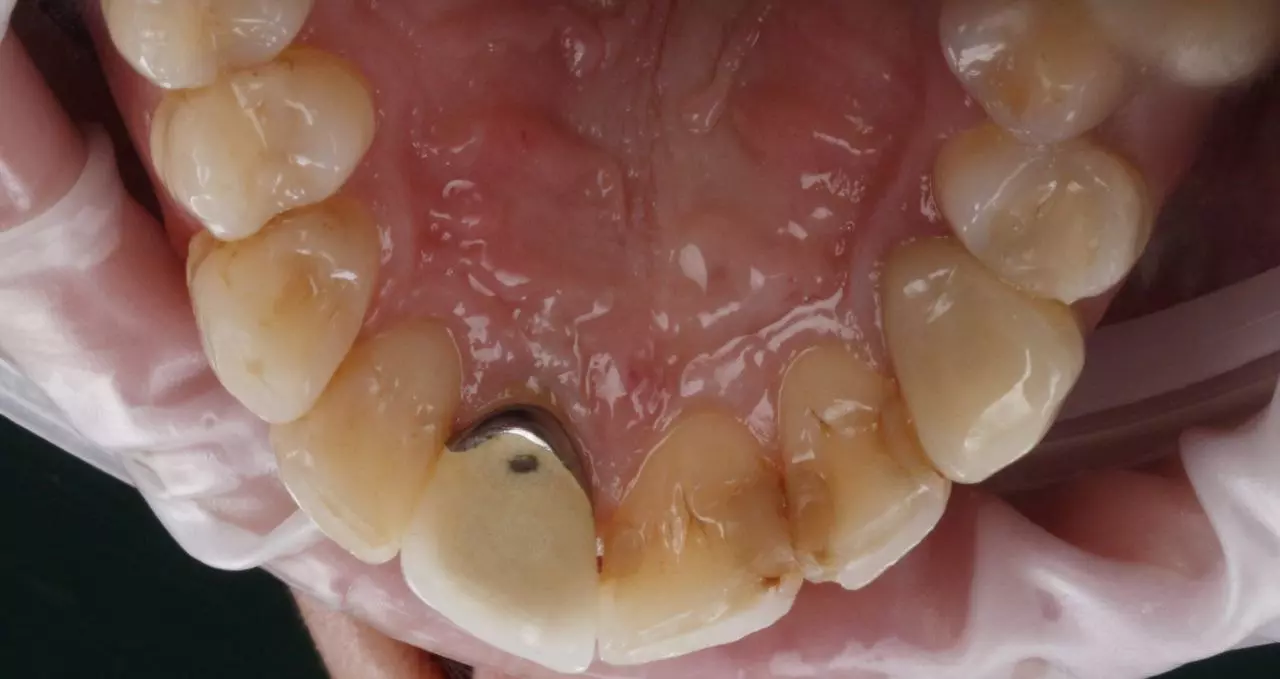

Художня реставрація 21.22.